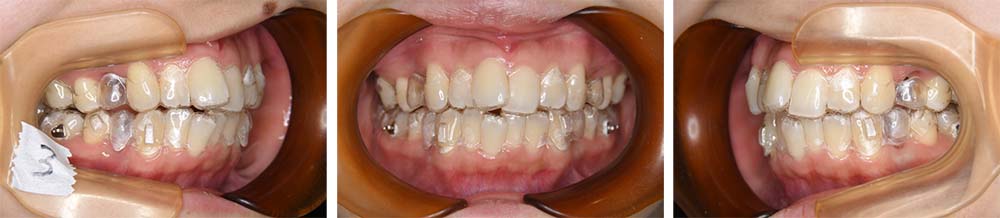

前歯が少し重なっている前歯部叢生を主訴として来院された。初診時ご相談時には口元に対しての要求はなかったが、口元の突出(俗にいうゴボ口)とガミースマイルについての説明をしたところ、治療対象とすることを希望された。分析の結果、上下顎前突と診断した。上下顎小臼歯抜歯を行っていただき、矯正用アンカースクリューを併用し上下顎舌側マルチブラケット装置を使用して動的治療を行った。叢生の改善と上下顎前歯の後退が十分に行われた。下口唇はE-ラインから+1㎜程度であったが、上口唇はE-ライン上まで後退させることができた。また、前歯の後退方向にも工夫を加えたことから、ガミースマイルもある程度改善した。動的治療期間2年1か月間。

治療前

治療後